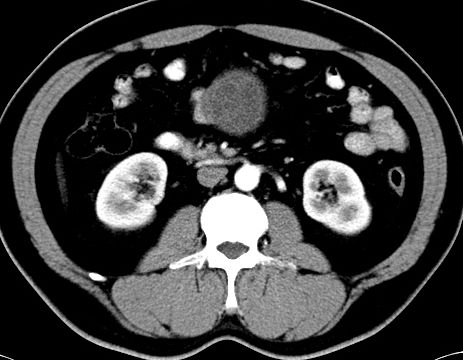

(腹腔)神经鞘瘤

男,48岁,间断性下腹不适1年。

手术探查

:距回盲部28厘米处肠系膜根部可见5*7cm左右包块,质中等硬度,活动度尚可,肝、胆、胰、脾肾未见明显异常。

病理

:(腹腔)

神经鞘瘤

,伴出血、坏死及囊性变,伴淋巴结反应性增生。

免疫组化结果

:sma(-), desmin(-), cd117(-), s-100(+++), nf(-),vimentin(+++).